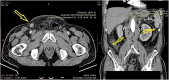

The presence of lymph node metastases in prostate adenocarcinoma is a poor prognostic sign, and mortality rates are often high. Inguinal lymph node metastases are an unusual presentation of advanced disease, and they can be easily misinterpreted with other diseases. We present a case of a 63-year-old patient with no previous symptoms and signs of prostate disorder with a right-sided inguinal lump and abdominal pain. The CT scan showed right inguinal and retroperitoneal lymphadenopathy. Elevated PSA serum levels, digital rectal examination, and skeletal scintigraphy with 99mTc-MDP favored the diagnosis of metastatic prostate adenocarcinoma. Since the patient denied prostate biopsy, a dissection of the right inguinal nodes was performed. Histopathological findings confirmed metastatic prostate adenocarcinoma. The treatment was hormonal and bisphosphonate therapy, with objective posttreatment improvement. Based on this case, it can be concluded that inguinal and generalized lymphadenopathy are potential initial manifestations of metastatic prostate adenocarcinoma in male patients.